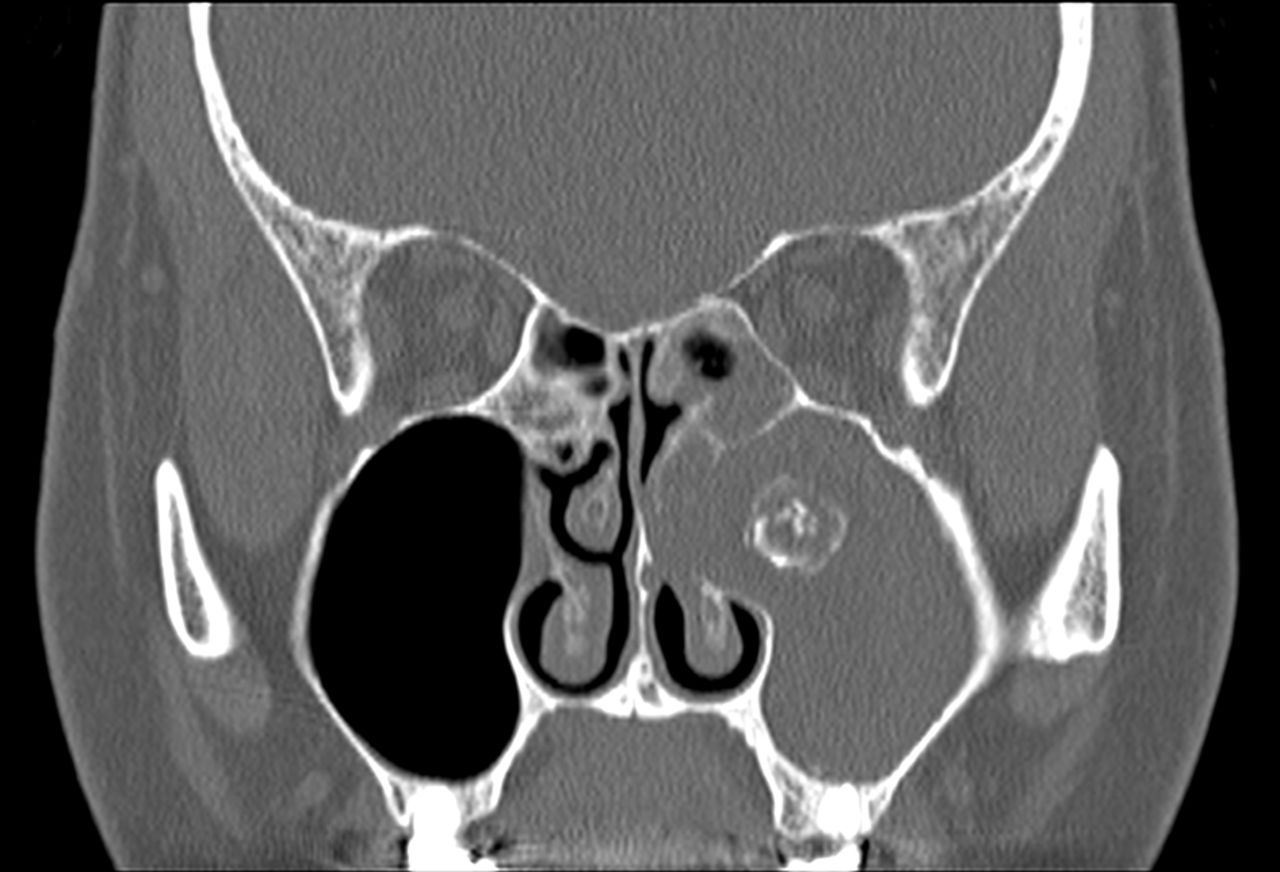

Il FUNGUS BALL:

Si tratta di una forma di sinusite cronica causata dall’accumulo di materiale fungino all’interno di un seno paranasale, più spesso il seno mascellare. Nella maggior parte dei casi, rimane confinato al seno senza invadere i tessuti circostanti.

I sintomi possono essere lievi o aspecifici e includono ostruzione nasale, secrezioni maleodoranti, dolore o senso di peso al volto, spesso da un solo lato. Talvolta la condizione viene scoperta casualmente durante esami radiologici.

La diagnosi si basa su TC dei seni paranasali, che mostra caratteristiche tipiche come aree iperdense all’interno del seno. Il trattamento è chirurgico e consiste nella rimozione del materiale fungino e nel ripristino della normale ventilazione del seno. Dopo l’intervento, la guarigione è generalmente completa senza necessità di terapia antifungina sistemica.